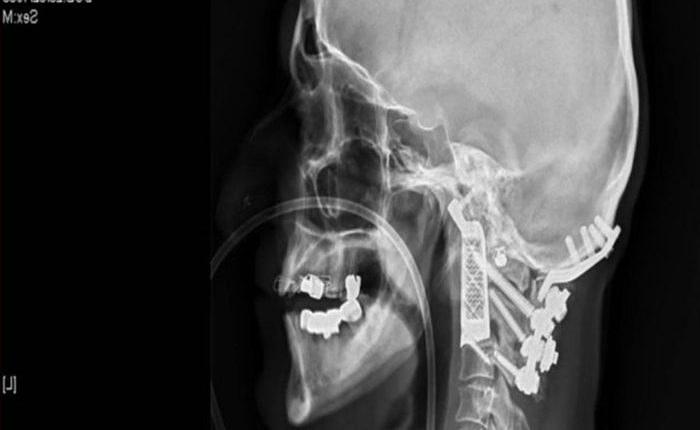

Tačiau gydytojai į pagalbą pasitelkė šiuolaikines technologijas. Jie 3D spausdintuvu atspausdino visas žmogaus kūno struktūros ypatybes atkartojantį implantą ir atliko operaciją, pakeisdami pažeistus slankstelio fragmentus dirbtiniais.

15 valandų trukusi operacija pacientui pagerino sveikatą ir gyvenimo kokybę. Implanto dėka vyras dabar vėl gali pasukti galvą ir pakelkite rankas.